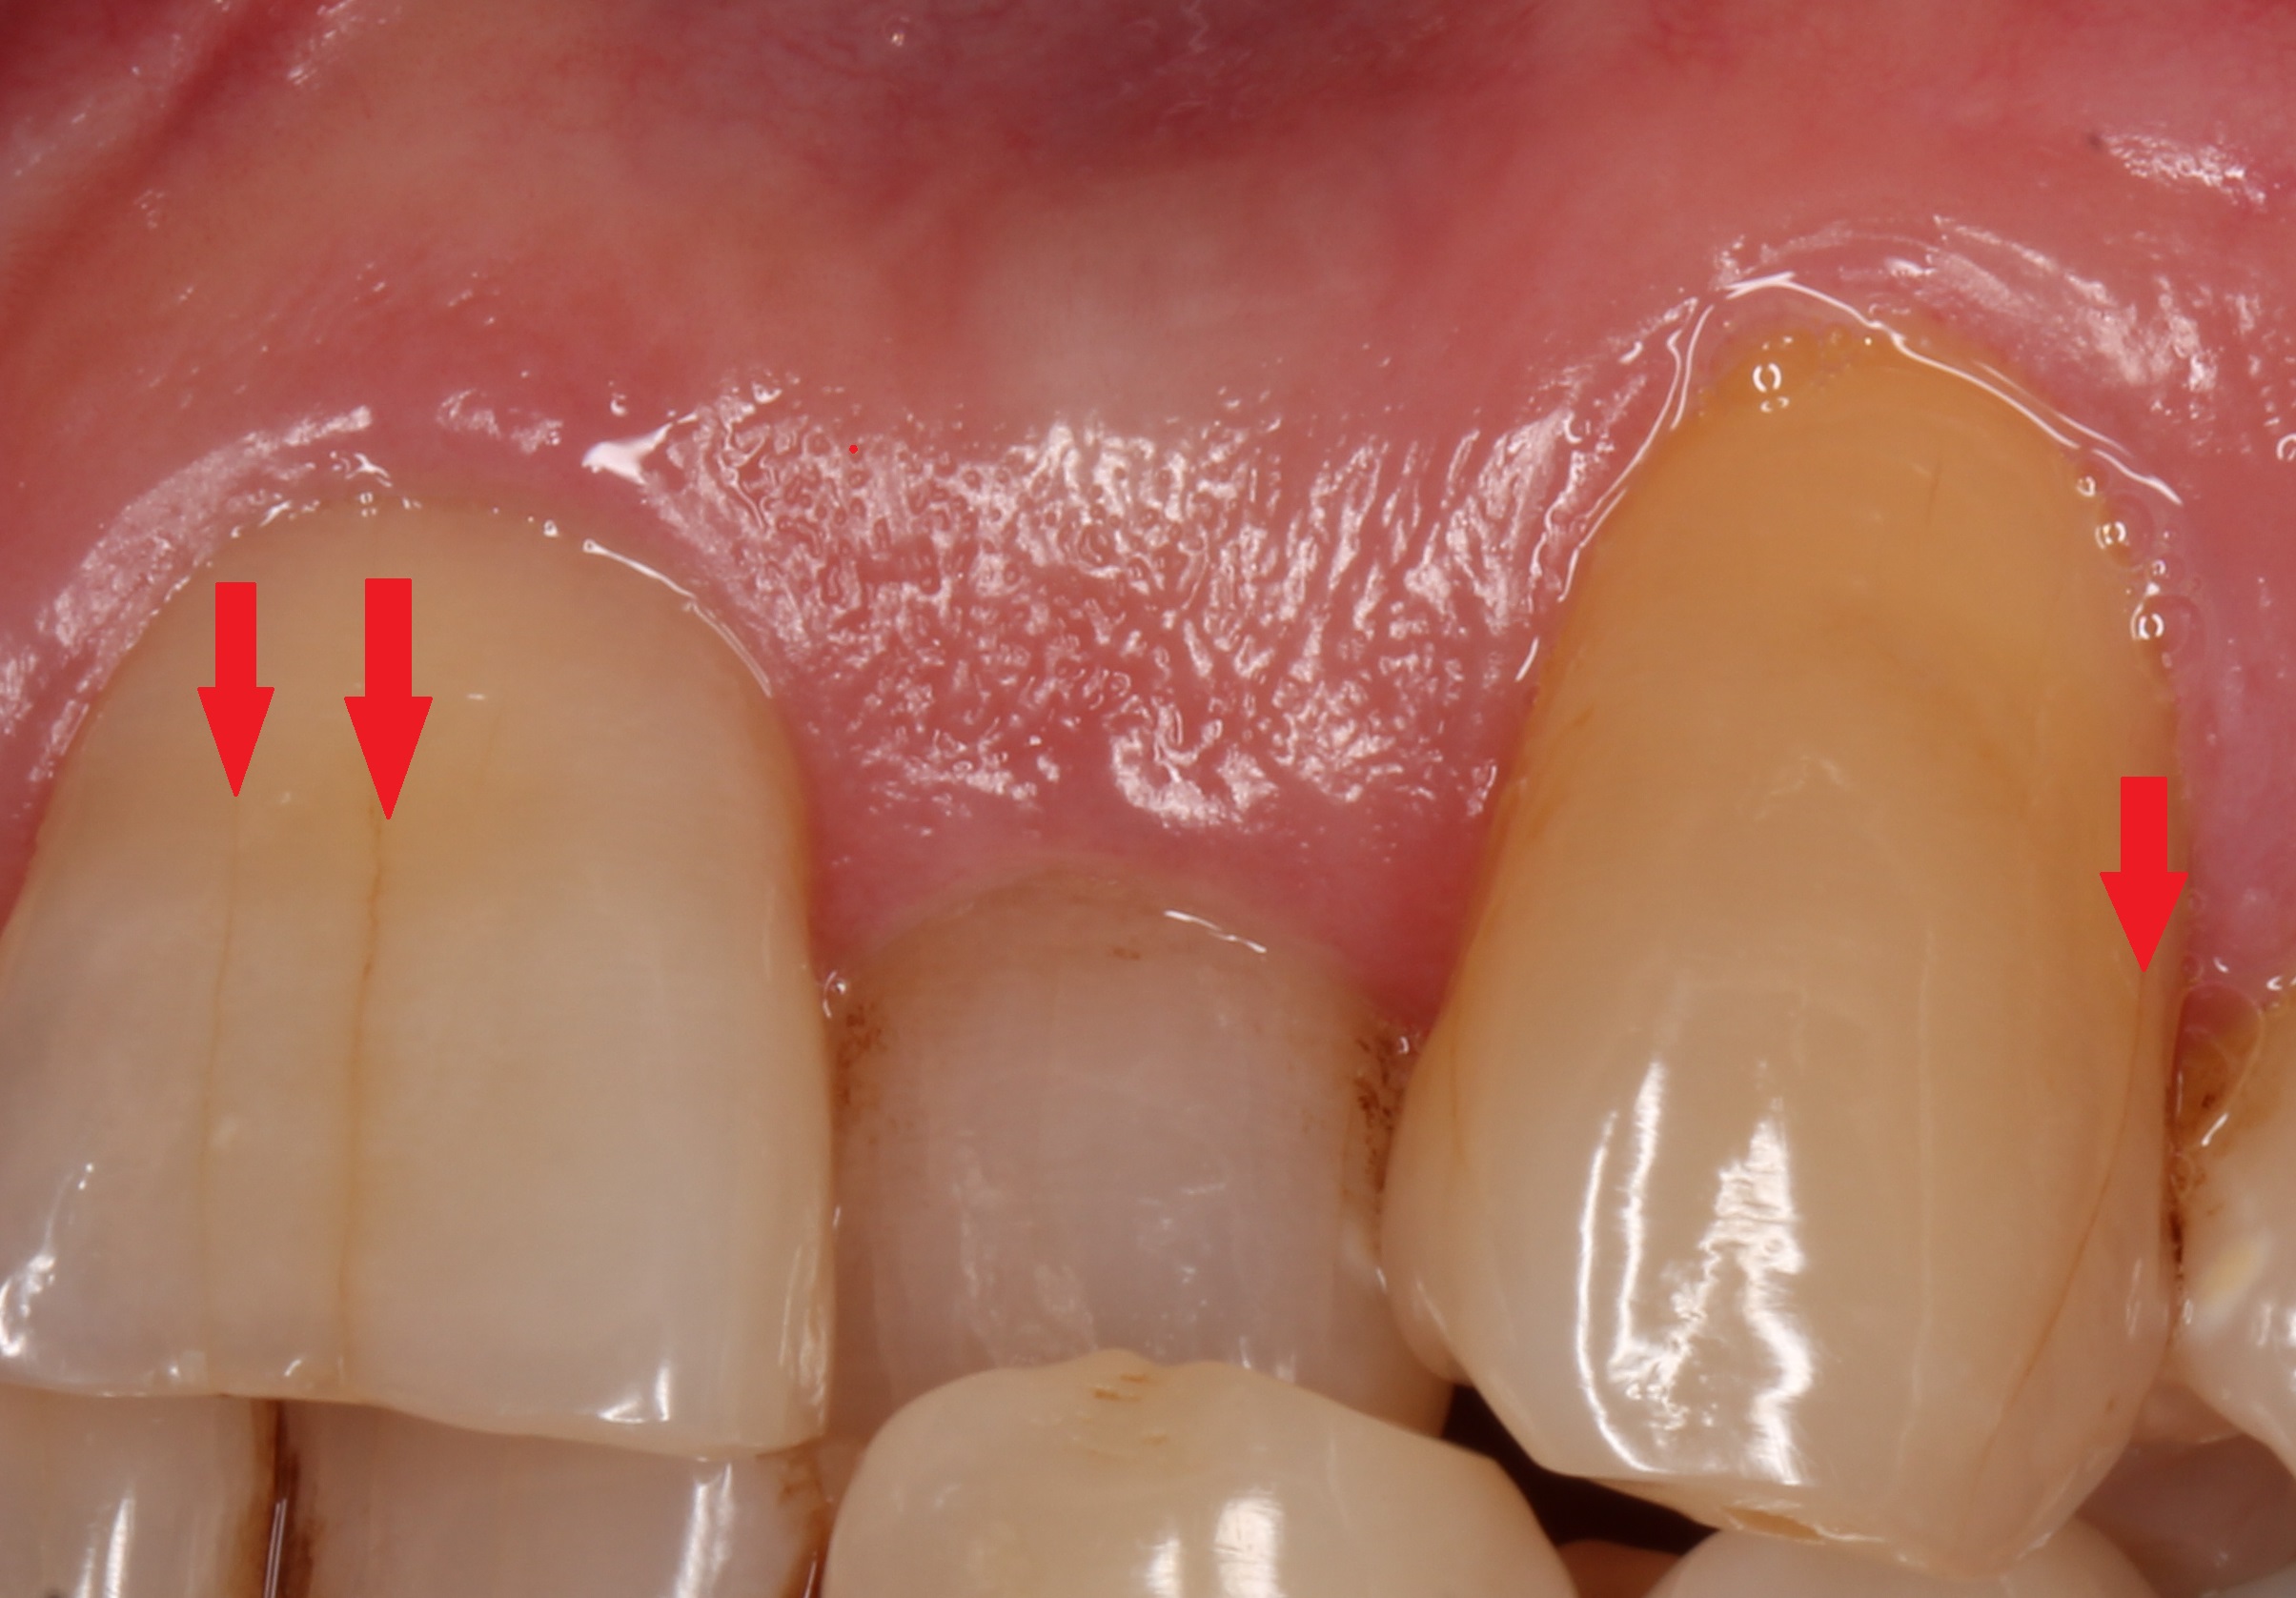

④歯のヒビ(マイクロクラック)

歯に負担がかかると、細かいヒビが入ることがあります。明るい場所で見たり、光を当てると見えやすいです。

⑤歯ぐきが下がる

⑥歯ぐきの際の段差(楔状欠損)

歯ぎしりで応力が集中すると「歯茎の際」の部分が欠けてしまいます。

楔状欠損・アブフラクションと呼ばれ、知覚過敏の原因になります。